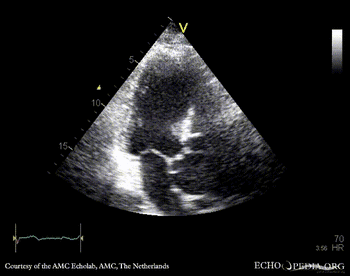

Aortic dissection type A

PSAX A5CH: dilated aortic root, dissection flap in ascending aorta